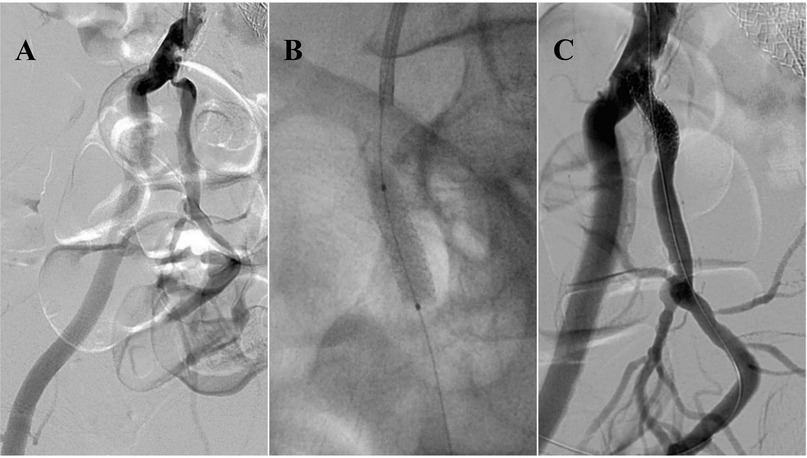

A Narrative Review of Endovascular Treatment in Addressing Arterial and Venous Erectile Dysfunction

Erectile dysfunction (ED) is a worldwide health concern and clinical condition for men, leading to high medical costs and imposing significant emotional and psychological burdens on sufferers annually. ED is associated with multiple causes, including psychological factors and organic issues such as arterial insufficiency and venous leakage. Endovascular treatments have emerged as promising options for managing ED, offering minimally invasive procedures that can improve blood flow to the penis and restore erectile function. Different endovascular interventional approaches have been implemented with varying success rates and therapeutic impacts, and efforts continue to optimize these methods (both arterial and venous) for maximum effectiveness and minimal invasiveness. This narrative review aims to provide an overview of endovascular treatments for arterial and venous types of ED, discussing their mechanisms of action, efficacy, safety, and future directions.